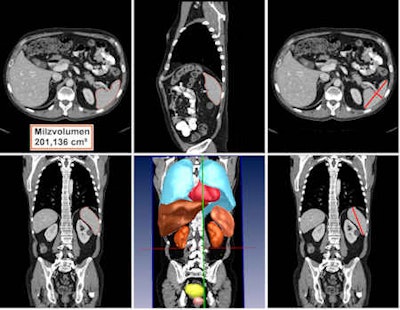

Automated detection and volumetry of spleen (delineated with red boundary lines) in axial (top left), sagittal (top center), and coronal plane (bottom left). Automated detection and volumetry of several organs in 3D view (center bottom). Top left and top right show manual measurements of the spleen. All images courtesy of Dr. Matthias Hammon.Since it's important for radiologists and clinicians to be able to track splenic volume over time, the researchers sought to develop a fast and accurate technique for automated detection and volumetric segmentation of the spleen on CT scans.